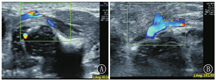

第一步:先用超声监测大隐静脉走行情况,观测大隐静脉与股静脉夹角情况,选择二者夹角较小的一侧肢体置管(图2)。第二步:获取下腔静脉和降主动脉平行切面。新生儿平卧位,探头置于近腋中线处、上界约与第10肋平齐、与肋骨垂直进行扫描,必要时可适当向前或向后移动及偏转探头方向(10°左右),即可获得下腔静脉和降主动脉平行切面。第三步:获取下腔静脉汇入右心房切面。新生儿平卧位,探头置于剑突下、与胸壁垂直获取剑突下左肝正中矢状切面,然后探头稍向右偏转(5~10°),即可获取下腔静脉汇入右心房切面,进而测得PICC尖端至右心房入口处距离(图3)。

通常新生儿PICC置管首选下肢静脉(大隐静脉)置管,经下肢大隐静脉置管堵管、感染发生率低,不仅一次性置管成功率高,还可降低PICC总并发症的发生率,尤其是异位的发生率[12,13,14]。鉴于此,本课题组在临床中摸索出下肢置管前先用超声监测血管情况,再决定从哪侧肢体置管,发现大隐静脉与股静脉夹角越大导管通过越困难,夹角越小导管越容易通过。因此,北京市朝阳区妇幼保健院新生儿监护病房自2019年以来下肢静脉置管均采用此方法,不仅缩短了置管时间,还减少并发症,尤其是机械性静脉炎的发生。